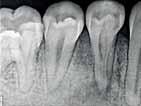

The Dental Panoramic Tomogram (DPT) confirmed the presence of all permanent teeth including the developing third molars (Figure 3). Root morphology appeared normal. The upper right central incisor had a root canal filling. The upper standard occlusal

radiograph revealed that the upper right central incisor had an adequate root filling with no periapical area. In the cephalometric assessment (Figure 4), the ANB value of 7° suggested a moderate Class II skeletal pattern. The vertical proportions were within normal values. The upper incisors were proclined at 122° and the lower incisors were of average inclination at 94°. The interincisal angle was reduced at 119°. The lower incisor to APo and the lower lip to E line were within normal limits.